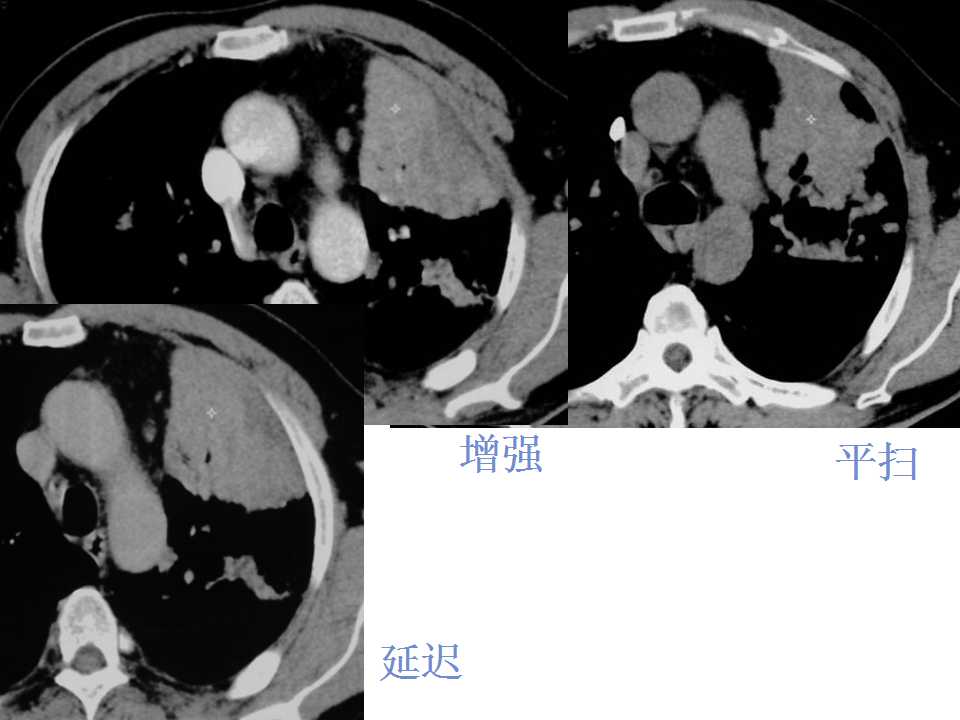

肺癌影像诊断